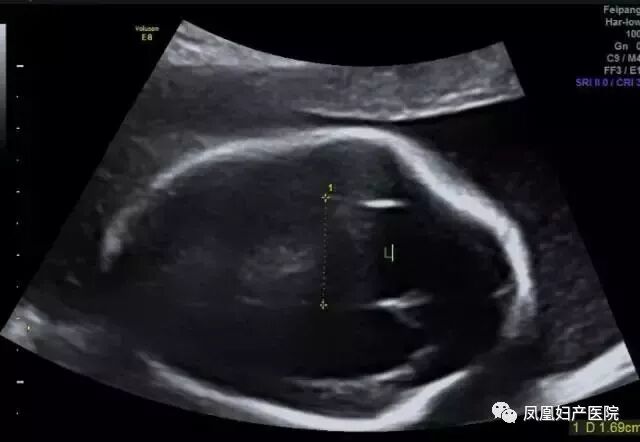

胎儿常见畸形检查图

(脊柱裂)

(左肾缺如)